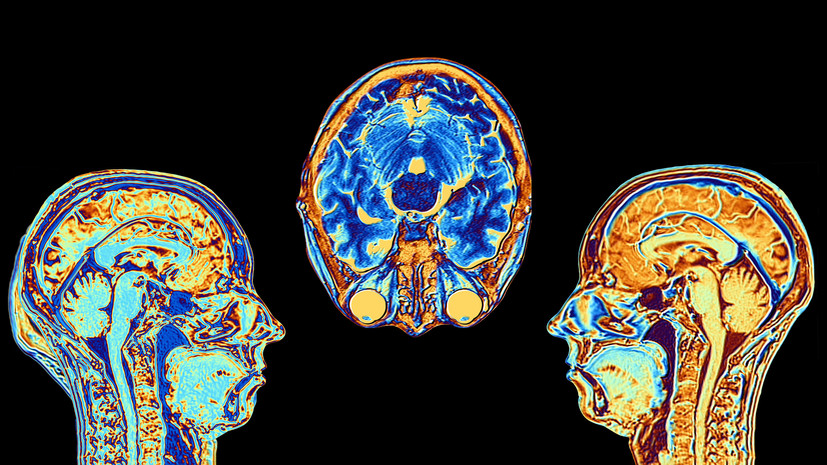

Российские учёные создали «карту жирности» человеческого мозга, которая показывает распределение липидов в разных его частях. Было установлено, что концентрация этих молекул в нём крайне неравномерна, также авторы работы выяснили, в каких отделах мозга преобладают те или иные липиды. Как считают авторы исследования, в перспективе эта карта поможет науке продвинуться в понимании причин и лечении ряда психических и когнитивных расстройств, таких как аутизм, шизофрения и болезнь Альцгеймера.

Учёные из Сколковского Института науки и технологий (Москва) составили полную карту расположения липидов в человеческом мозге. Исследователи установили, как именно в нём распределены различные типы жиров, которые входят в состав нервной ткани. Результаты исследования в перспективе помогут медикам лучше понять природу психических расстройств, а также нейродегенеративных заболеваний. Результаты исследования, поддержанного грантом Президентской программы Российского научного фонда (РНФ), опубликованы в журнале Nature Communications.